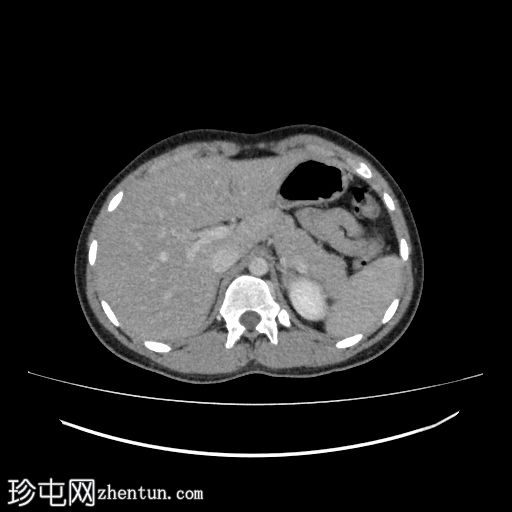

肾轴位

肾实质期

1.jpg

右侧输尿管近端至中段在L3-L5椎体水平向内侧移位

输尿管在L3-L4椎体水平轻度节段性隆起

该段输尿管走行于下腔静脉后方,然后从主动脉和下腔静脉之间向内侧走行,远端转向外侧,正常开口于膀胱输尿管连接处

右侧输尿管走行异常,属于环腔静脉/腔后输尿管(2型)

影像学上,该畸形可分为两种类型。 1 型是较常见的类型,表现为近端输尿管明显向内侧偏移,呈经典的“S”形或“鱼钩”形,并伴有肾积水。2 型较少见,表现为输尿管袢位置较高,梗阻程度较轻,呈镰刀状。过去主要通过静脉尿路造影进行诊断,而现在 CT 尿路造影和 MR 尿路造影能够更清晰地显示输尿管与下腔静脉的关系以及梗阻程度。